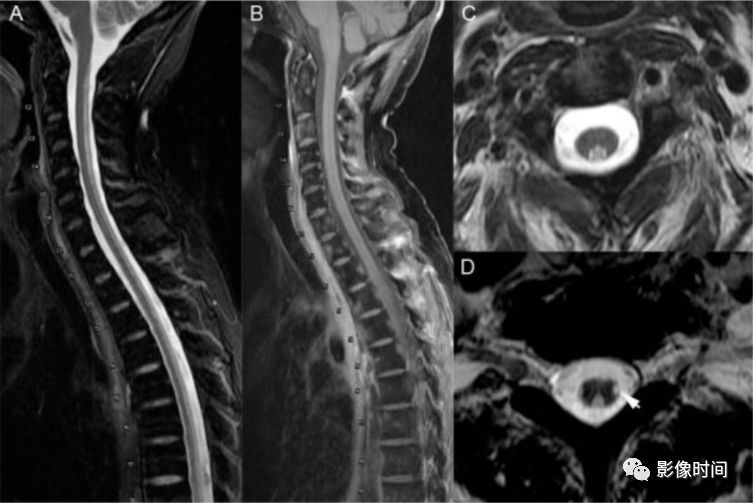

硬脊膜动静脉瘘 (spinal dural arteriovenous fistula,SDAVF):供应脊膜或神经根的细小动脉,在椎间孔处穿过硬膜与脊髓引流静脉相通,导致脊髓回流受阻。病因不明,成人-老年人胸腰段多见,缓慢起病,进行性加重。

MRI:

矢状位 T2WI 发现长节段高信号

矢状位 T2WI 脊髓周围流空低信号血管影

部分可见强化,提示血脑屏障破坏

脊髓内长节段T2WI高信号,髓周可见多发点状流空血管,增强扫描出现强化

3、治疗相关

放射性脊髓病(Radiation myelopathy):一般为放疗后 1 个月至数年出现进行性麻木和虚弱±括约肌功能障碍,大多数情况下呈持续进展。镜下可见脱髓鞘、星形胶质细胞肿胀,血管内皮损伤、坏死,局部钙离子沉积,血管壁透明变性等。

脊髓肿胀

T1WI 呈稍低或低信号;T2WI 呈稍高信号

环形或不规则强化

晚期出现局灶性脊髓萎缩

T1WI 出现放射治疗后椎体黄骨髓置换,提示本病具有重要意义

脊髓长节段病灶,中心分布为主,T2WI高信号,注意椎体T1出现高信号